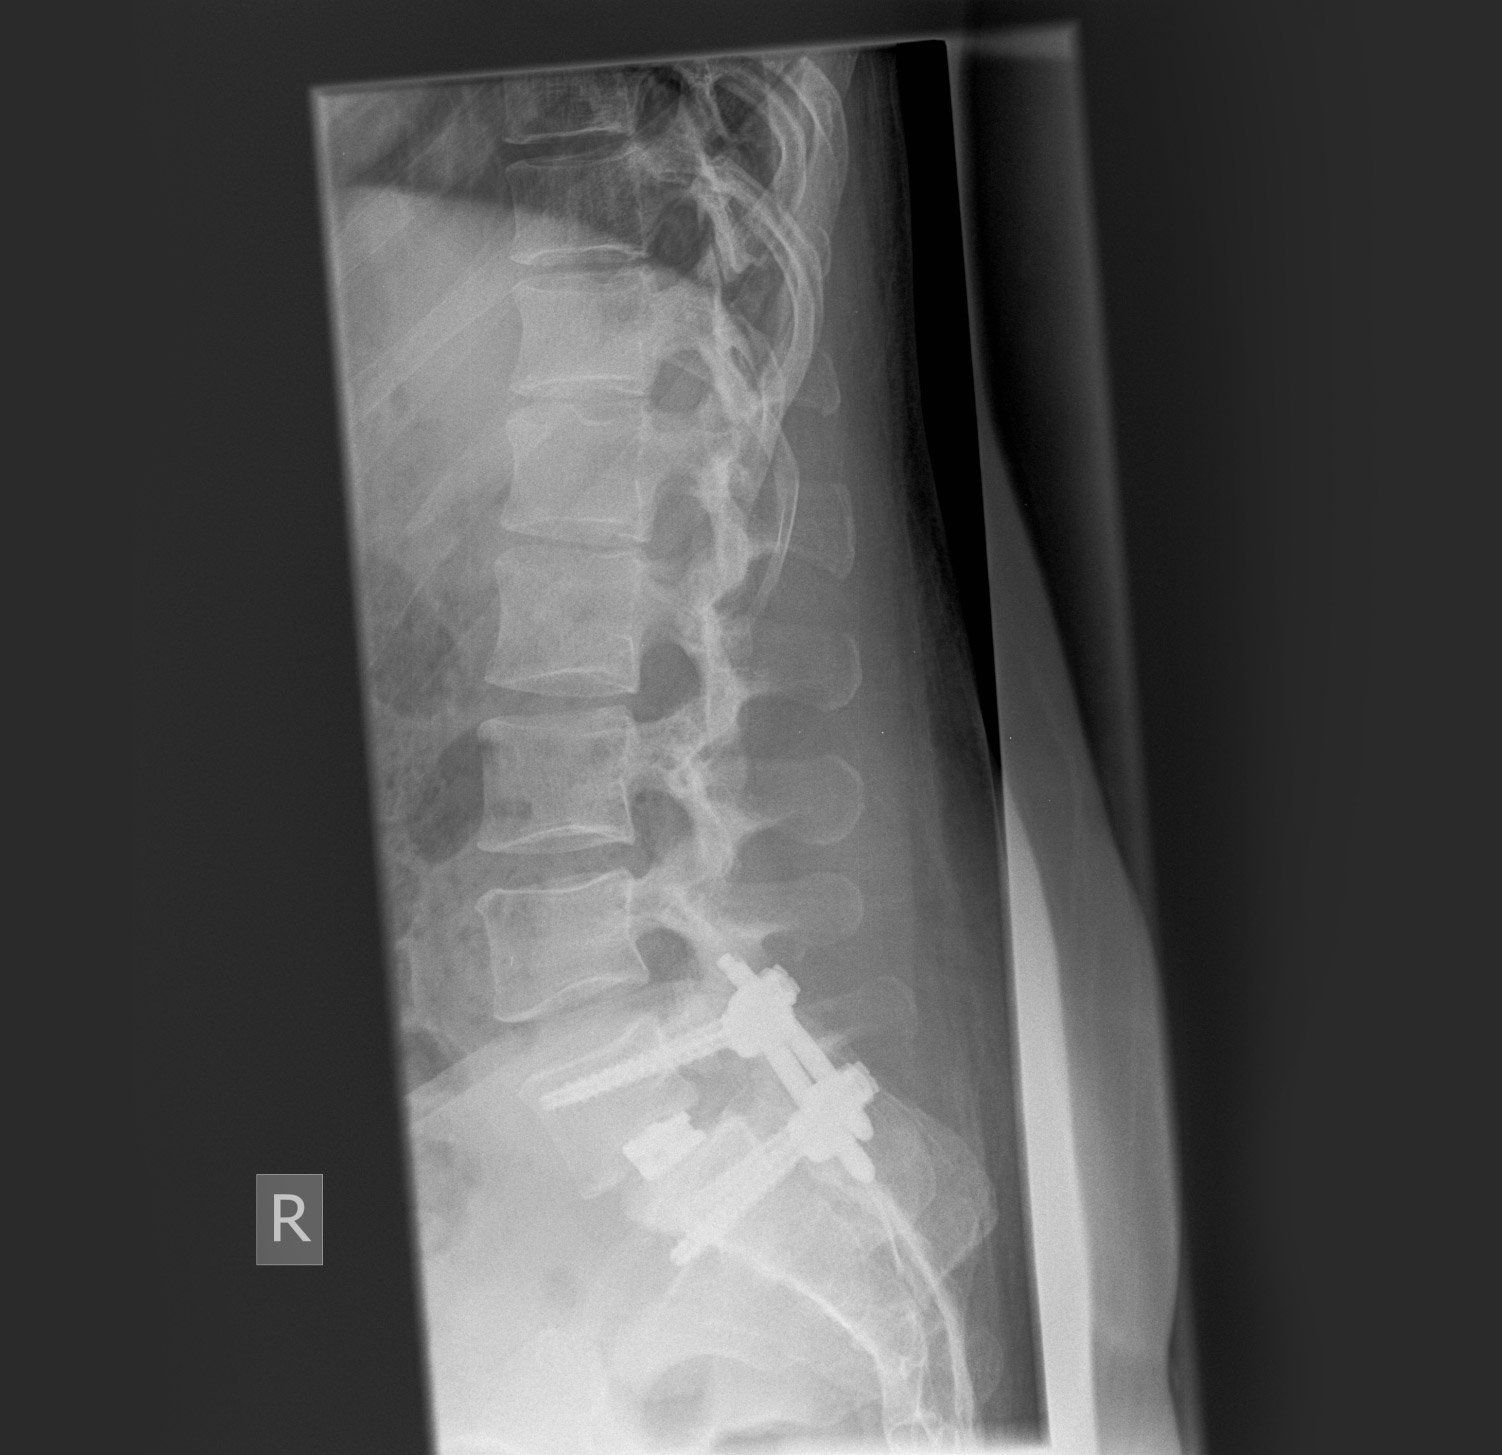

This is the post-surgery X-ray showing that the slip has been corrected and a metal scaffold has been placed into the bones either side of the slip. A cage with bone graft has been put into the disc space to complete the spinal fusion.

Metal work has been put into the spine to allow the spine to fuse to correct the defect and improve pain.